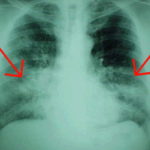

Fumare la marijuana sembra essere associato ad un aumentato rischio di tosse, produzione di escreato e dispnea, secondo una recensione pubblicata online il 3 luglio negli Annals of Internal Medicine.

I ricercatori hanno scoperto che in un’analisi aggregata di due studi prospettici, l’uso di marijuana era correlato ad un elevato rischio di tosse e produzione di espettorato (rapporti di rischio, 2.04 e 3.84, rispettivamente). In un’analisi congiunta di studi trasversali (uno con basso e tre con rischio moderato di bias), l’uso di marijuana era correlato con tosse, produzione di espettorato e dispnea (rapporti di rischio, 4.37, 3.4 e 1.56, rispettivamente ). I dati sulla funzione polmonare e la malattia polmonare ostruttiva non erano sufficienti.

“Le prove a bassa resistenza suggeriscono che fumare marijuana è associato a tosse, produzione di espettorato e respiro sibilante”, scrivono gli autori. “Le prove sull’associazione tra uso di marijuana e malattia polmonare ostruttiva e funzione polmonare sono insufficienti”.